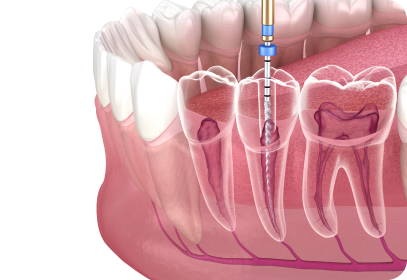

신경치료

충치로 인해 치수가 노출되었을 경우, 치수를 덜어내 통증을 없애고 그 자리에 멸균 재료로 충전하여 통증과 충치 확산을 막아주는 치료입니다.

재신경치료

치아의 뿌리에 재감염이 일어났거나 새로운 충치로 인해 염증이 생겼을 때 재신경치료를 통해 남아있는 염증을 없애주는 치료입니다.